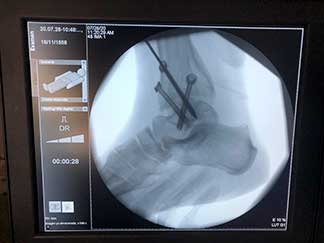

Vasculares, nerviosas, articulares y óseas que se traducen en fracturas conocidas como edema óseo.

Artículo de trabajo con equipo de Primera División “Tuzos de Pachuca”

Durante mi entrenamiento en mi segundo fellow en cirugía articular y lesiones deportivas, tuve la oportunidad de hacer una rotación en el hospital CEMA by FIFA (Centro de Excelencia Médica en Altura) en Pachuca Hidalgo, donde brindé atención médica y quirúrgica en las instalaciones de la Universidad a pacientes deportistas profesionales y de alto rendimiento, miembros del equipo de fútbol “Tuzos de Pachuca”.